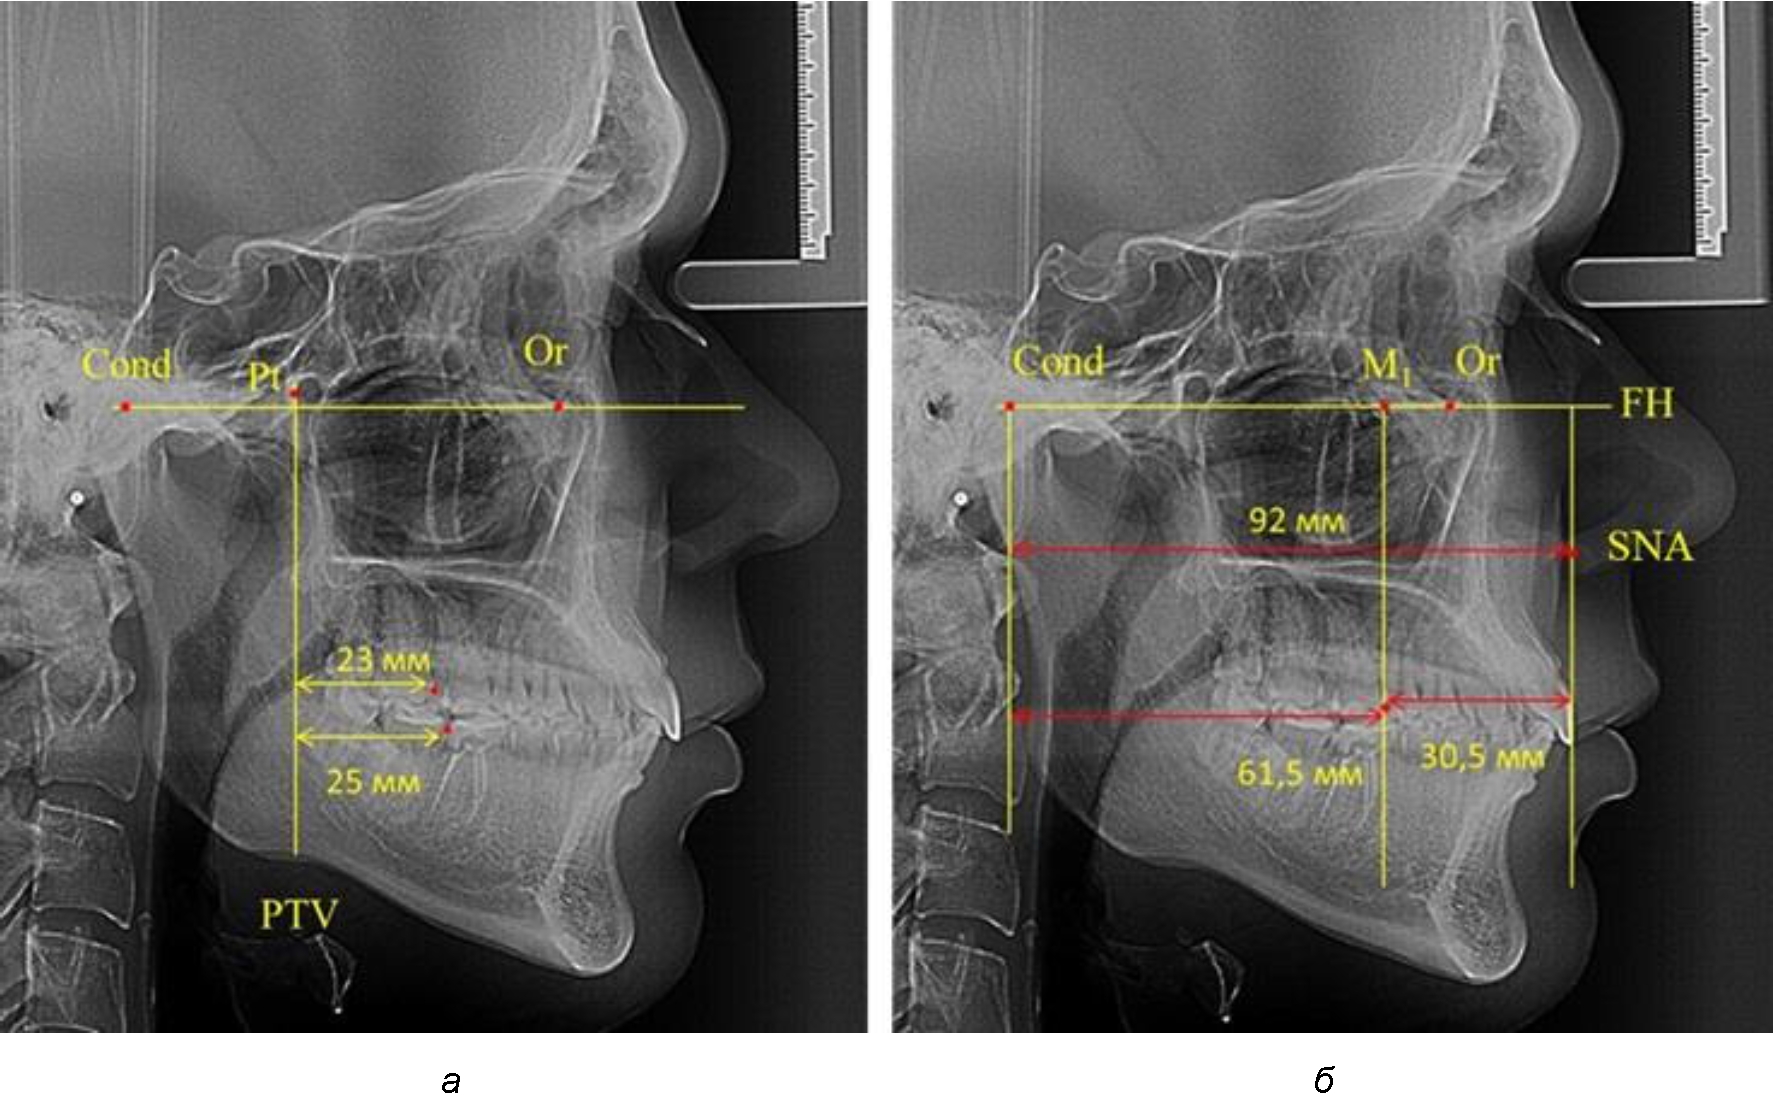

Согласно указанному методу на рентгенограммах проводили Франкфуртскую горизонталь. Учитывая мнения специалистов относительно ориентиров для построения и вариабельность положения наружного слухового прохода, в качестве задней точки использовали верхнюю выпуклость суставной головки нижней челюсти («Cond»). Передняя точка традиционно располагалась на нижнем крае глазницы и определялась как орбитальная точка Or.

Находили положение точки Pt, которая располагалась на пересечении нижнего края круглого отверстия и задней стенки крыловидно-верхнечелюстной щели, и перпендикулярно к Франкфуртской горизонтали проводили крыловидную вертикальную линию, которую принято обозначать как плоскость PTV. Расстояние от крыловидной вертикальной плоскости PTV до дистальной поверхности верхнего первого постоянного моляра определяло его положение, которое, по мнению R. E. McDonald, соответствовало возрасту пациента, увеличенному на 3 мм.

При проведении анализа к Франкфуртской горизонтали проводили передний и задний перпендикуляры. Передний спинальный перпендикуляр проходил через выступающую точку передней носовой ости (spina nasalis anterior – SNA), а задний суставной перпендикуляр опускали из кондилярной точки Cond. Молярный перпендикуляр проводили через медиальную поверхность первого постоянного моляра. Указанная вертикаль отделяла замещающие зубы постоянного прикуса от добавочных зубов (постоянных моляров), что вполне логично для анализа положения первых постоянных моляров в гнатическом комплексе (рис. 1).

Рис. 1. Метод определения положения первых верхних моляров по Ralph E. McDonald (а) и по предложенному методу (б)